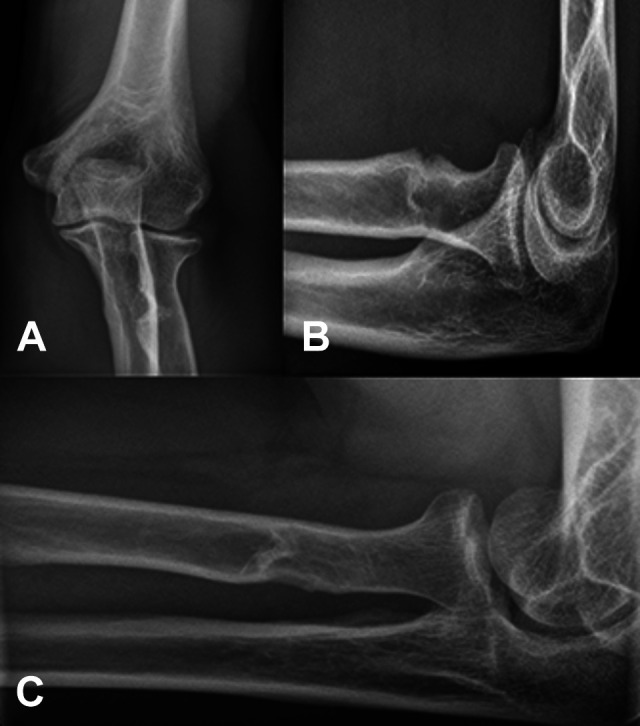

Figure 5.

Radiographs of the left elbow in (A) anteroposterior, (B) lateral, and (C) Coyle views 15 years postoperatively without any heterotopic ossification.